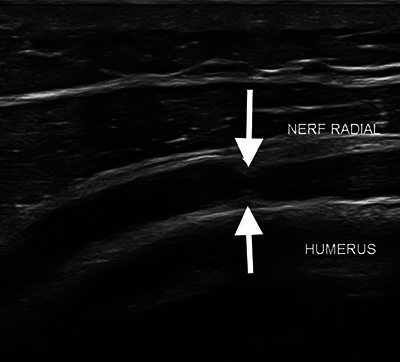

教学要点:对于有不明原因的周围神经病变症状的患者,应考虑沙漏样收缩性神经病变,因为影像学检查可能会显示神经收缩,但没有内在或外在压迫的证据。

Teaching point: Hourglass-like constrictive neuropathy should be considered in patients with unexplained peripheral neuropathy symptoms, as imaging may show nerve constriction without evidence of intrinsic or extrinsic compression.